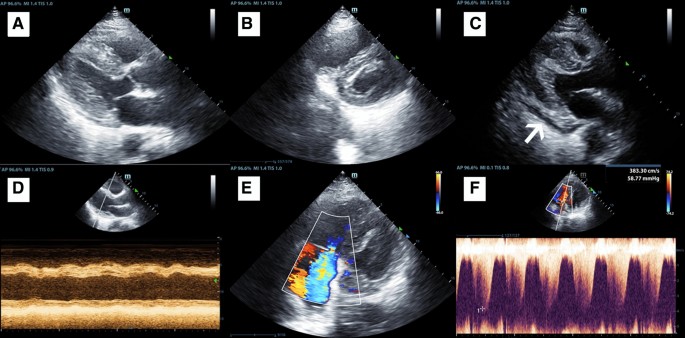

Fig. 2

figure 2

Echocardiographic images of patients with COVID-19. a Diffuse thickening of the left-ventricular wall. b Right-ventricular enlargement and left-ventricular wall thickening. c A small amount of pericardial effusion behind the left-ventricular posterior wall (white arrow). d M-mode graph of the left-ventricular basement showed ventricular wall dyskinesia and a decreased left-ventricular ejection fraction. e Color Doppler showed moderate-to-severe tricuspid regurgitation. f Continuous wave Doppler showed pulmonary hypertension

Due to considerations of reducing nosocomial infection and personnel shortages, we performed echocardiography and electrocardiography only for patients with severe disease, clinical symptoms, or a previous heart history (Table 3; Fig. 2). A total of 57 patients receive echocardiography, including 31 in ICU group and 26 in non-ICU group. The most common manifestations on echocardiography were a thickened interventricular septum dimension (IVSd) (12 [39%] vs 1 [4%]), a thickened left-ventricular posterior wall depth (LVPWd) (12 [39%] vs 1 [4%]), a reduced left-ventricular ejection fraction (LVEF) (5 [16%] vs 0 [0%]), and pulmonary arterial hypertension (9 [29%] vs 0 [0%]). Measurements of the IVSd, LVPWd, and pulmonary arterial systolic pressure (PASP) significantly differed between the groups, which were higher in the ICU group. The measurements for the ICU vs non-ICU patients were as follows: IVSd (11.00 mm [10.00–13.00] vs 10.00 mm [9.00–10.00]), LVPWd (11.00 mm [10.00–12.00] vs 10.00 mm [9.00–10.00]), and PASP (34.53 ± 19.07 mmHg vs 20.94 ± 4.02 mmHg). The left atrium (LA) and left-ventricular diastolic diameter (LVDd) did not show significant differences between the two groups. Overall, 10% of the patients in the ICU presented with right heart enlargement, a thickened right-ventricular wall, decreased right heart function, and pericardial effusion. In addition, the measurements for left-ventricular diastolic function in the COVID-19 patients in this study were normal.